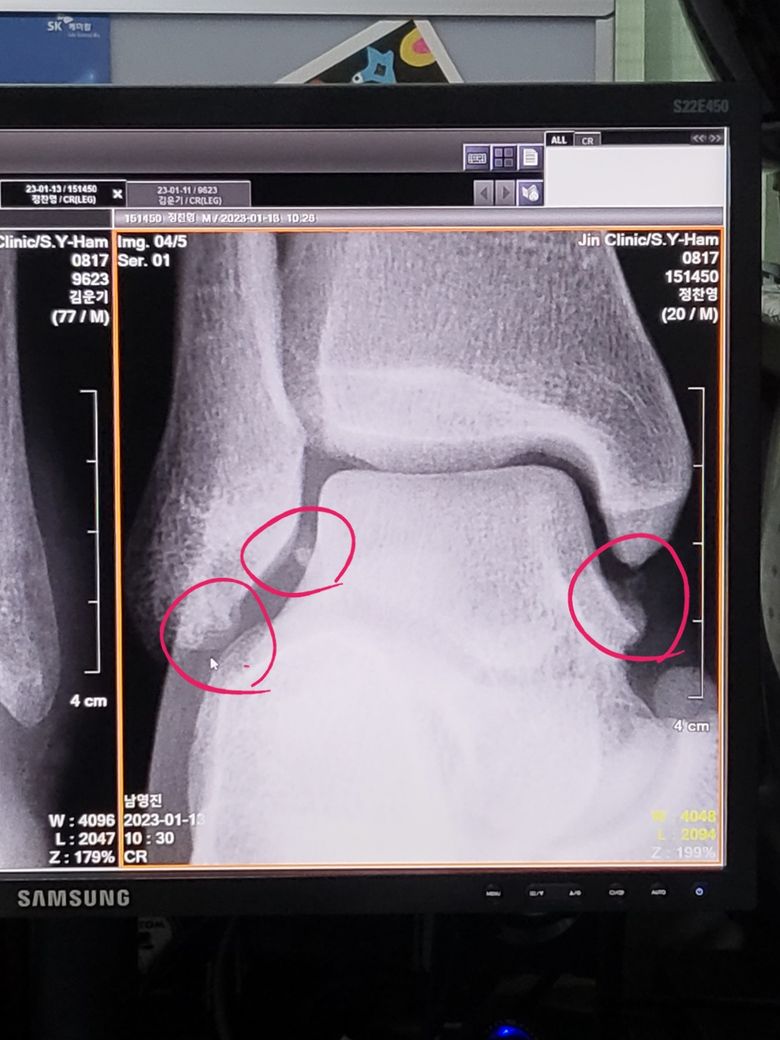

우측 발목 엑스레이 어떤 이상이 있는 건가요?

우측 발목이 아파서 병원에 가서 엑스레이를 찍었는데 동그라미 친 부분에 문제가 있다고 해서 mri를 찍으라 하는데 대충 무슨 문제인지 알 수 있을까요? 그리고 수술할 정도로 큰 문제인가요?

• 안녕하세요. 박주영 의사입니다. 관절 안에 작은 뼈조각이 보이는 상황으로 정상적인 상황은 아닙니다. 골절에 의한 뼈조각일 수도 있고 아니면 관절면에서 떨어진 뼈조각 가능성도 있습니다. 그리고 양쪽에 있는 뼈조각들은 인대가 뜯어지면서 물려서 떨어진 뼈조각이 있을 수 있으므로 MRI로 인대 와 관절면을 확인해 보아야 하고 그 정도에 따라 수술을 해야 하는 경우도 있습니다.

• 안녕하세요. 김선도 의사입니다.

인대 부착부위로 해당부위에는 엑스레이에서 보이는 골편이 보여서는 안되는데 현재 보인다는 것은 인대 파열이나 건열골절의 가능성이 있습니다.

잦은 발목외상이 있으셨다면 이로인한 인대손상의 가능성 및 관절내 유리체의 가능성이 높아보입니다.

MRI 및 CT 체크를 통해 인대손상 여부 및 연골손상의 가능성 까지 감별을 받아보시는 것이 좋겠습니다.